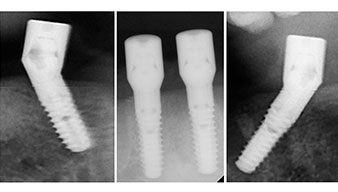

Para la planificación y la minimización del riesgo, se realizó una tomografía volumétrica tridimensional (TVD, Planmeca) que mostró que la calidad y la cantidad del tejido óseo era suficiente para la intervención quirúrgica y el tratamiento inmediato con el método Fast & Fixed. Siguiendo el protocolo de este método, se insertaron los implantes en la región de las piezas 35, 32, 42 y 45. Debido a la inclinación de hasta 45 grados de los implantes distales, el perfil de emergencia se desplazó hacia posterior y se generó un mayor polígono de soporte (fig. 3).

El protocolo quirúrgico de los implantes utilizados (SKY, bredent medical) prescribe una velocidad de 1 200/rpm para las perforaciones piloto (figs. 7-9).

Este valor se corresponde con la posición siguiente del ajuste predefinido en Implantmed. Aquí se aprecia la inclinación de aproximadamente 45 grados del contra-ángulo de W&H hacia medio caudal en la región de la pieza 45 para preservar el nervus mentalis. El foramen mentale sirve como orientación anatómica para todas las perforaciones en esta zona. Las perforaciones siguientes se realizaron con una velocidad reducida de 300/rpm (figs. 10 y 11).

Tanto el contra-ángulo como la pieza de mano S-11 de W&H disponen de refrigeración externa, lo que supone una ventaja, ya que la solución de NaCl llega exactamente al lugar preciso y, en caso necesario, también puede reajustarse. Los contra-ángulos y las piezas de mano pueden desmontarse, lo que resulta muy recomendable desde el punto de vista higiénico y de la capacidad de esterilización. Se implantaron cuatro implantes SKY de 4,0 x 14 mm. Los contra-ángulos y las piezas de mano pueden desmontarse, lo que resulta muy recomendable desde el punto de vista de la higiene y de la capacidad de esterilización. Se implantaron cuatro implantes SKY de 4,0 x 14 mm.